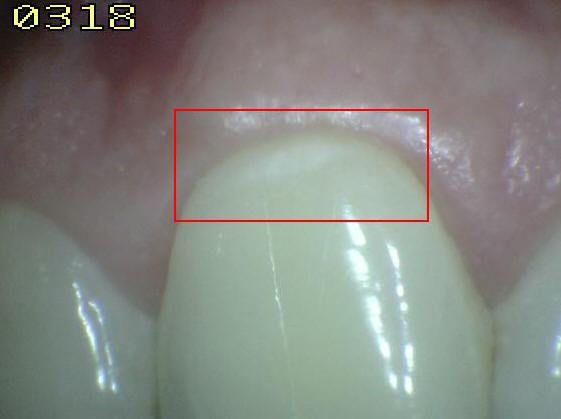

Código 3

(Caries Moderada): Ruptura

localizada del esmalte debido a caries sin dentina visible

- Una vez secadas durante aproximadamente

cinco segundos se observa una pérdida clara de la integridad

del esmalte, visto desde la dirección vestibular o lingual.

- En húmedo están presentes lesiones

blancas o decoloradas.

- En caso de duda, o para confirmar la

evaluación visual, la sonda IPC puede ser

utilizada

suavemente por la superficie para confirmar la pérdida de la

integridad de la superficie del esmalte.< 0,5 mm.